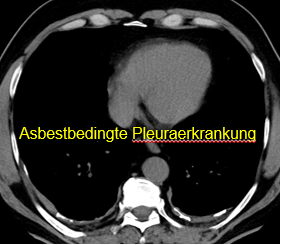

Berufsbedingte Lungenerkrankungen – fachradiologische Begutachtung

Bei berufsbedingten Lungenerkrankungen unterstützen wir die Diagnostik und Einordnung im Rahmen der klinischen Fragestellung. Dazu gehören – je nach Auftrag – beratungsärztliche Stellungnahmen sowie fachradiologische Gutachten.

Typische Themen:

- Asbestassoziierte Veränderungen.

Beispielhafte Aufnahmen verschiedener Erkrankungen

(Lungenklinik Lostau)